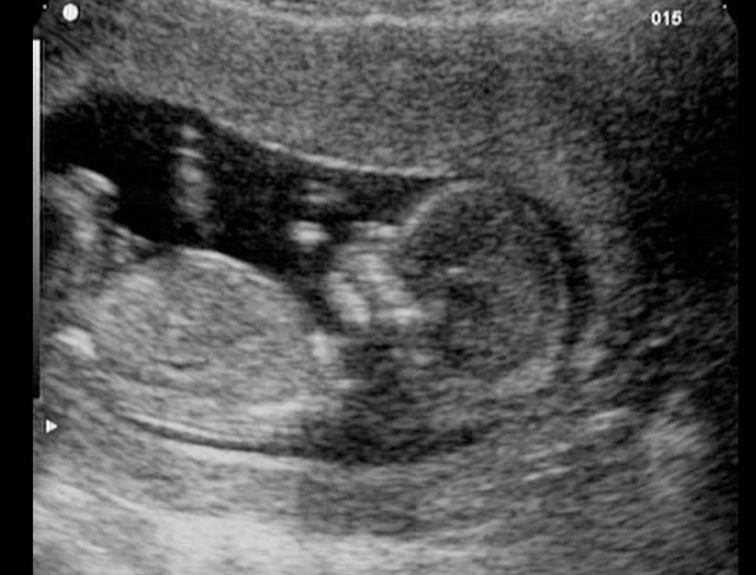

This is often the first detailed look at your baby, and it's breathtaking. The 12-week scan, sometimes combined with the First Trimester Screening (which assesses risk for chromosomal conditions), gives you a clear picture of that little occupant.

On the screen, you'll see your baby's location clearly within the amniotic sac inside the uterus. The sonographer will measure the baby from crown to rump to confirm your due date. They'll check for the presence of a nasal bone and measure the nuchal translucency—a small fluid space at the back of the baby's neck. An increased measurement can be a soft marker for certain conditions.

Beyond the medical checks, you'll get to see your baby in action. You might see the heart beating rapidly (around 120-160 beats per minute), watch the baby bring its hand to its mouth, or see it bounce gently against the uterine wall. It makes the whole thing feel wonderfully real.